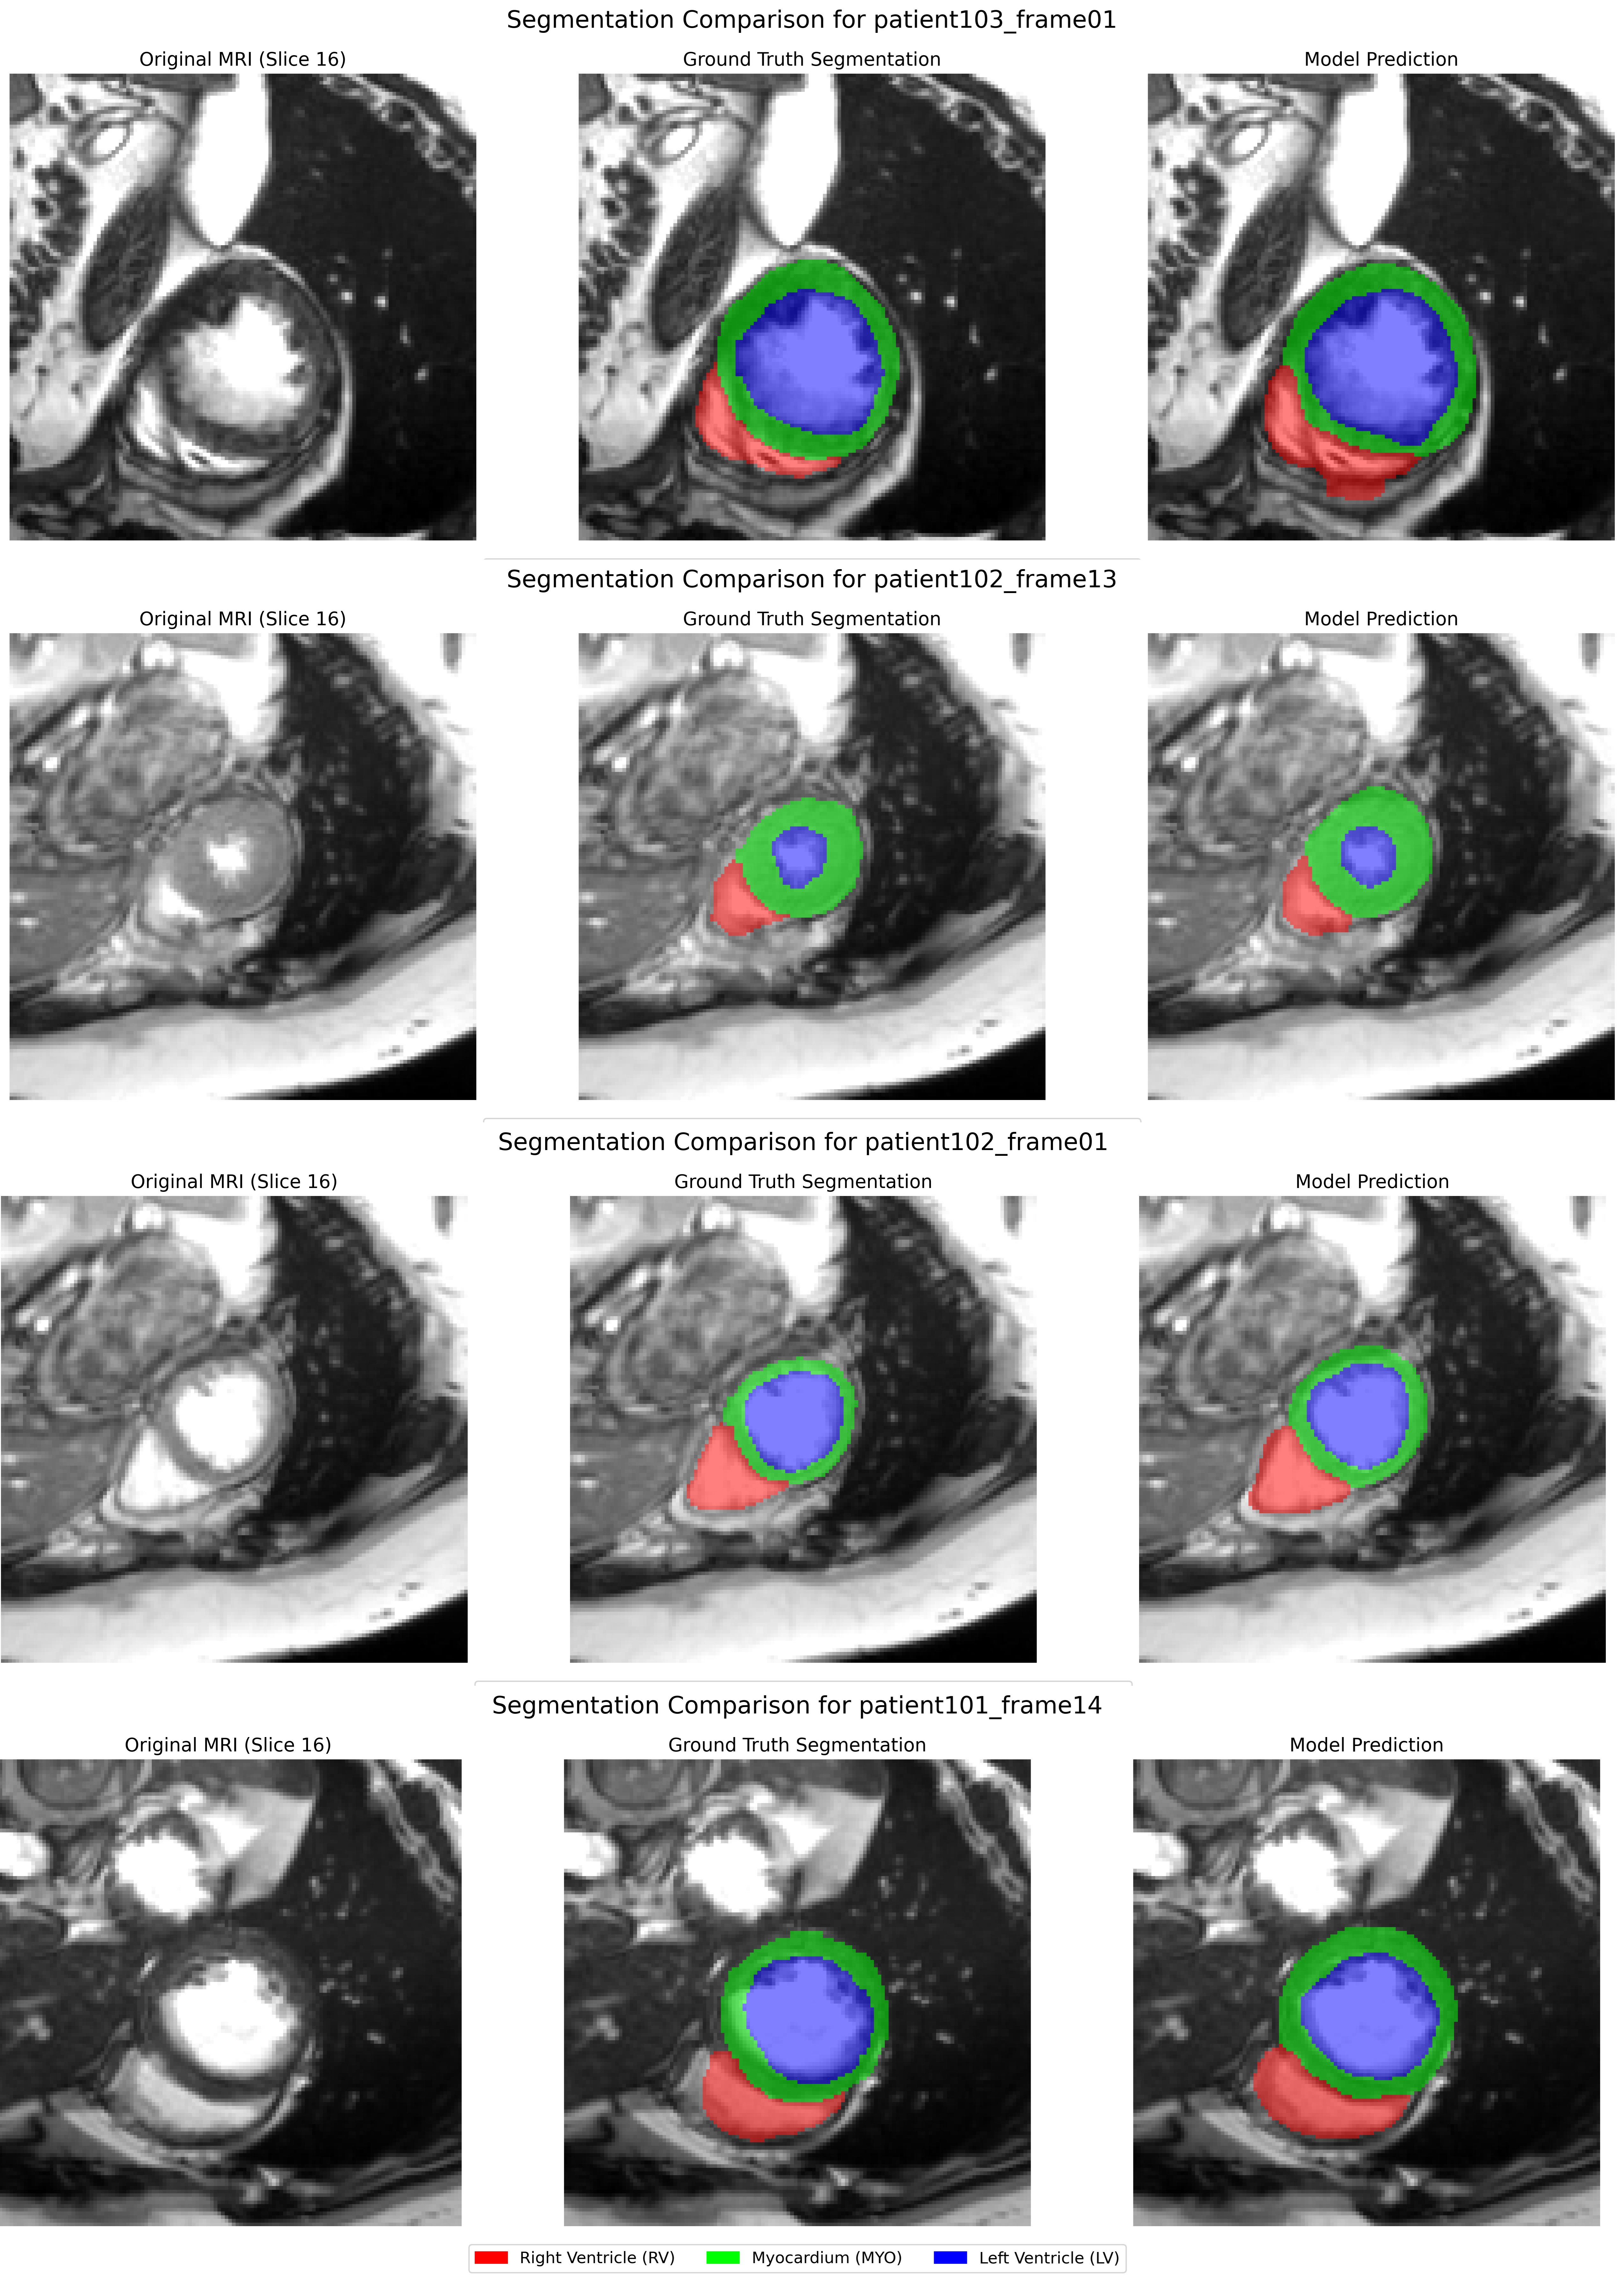

Visual inspection provides complementary insights. Figure 3 showcases representative examples from the TP_MFGC model. The predictions generally align well with the ground truth, accurately capturing the morphology of the RV, Myo, and LV across different patients and slice locations. The MFGC module’s ability to consider frequency information may contribute to the good delineation of structures even with subtle contrast variations. While boundary adherence appears good visually, the high quantitative HD95 suggests occasional localized errors might occur, perhaps at complex junctions or where frequency characteristics are ambiguous. In some instances, discrepancies might even relate to potential inconsistencies in the ground truth labels themselves.

Refer to caption

Figure 3: Qualitative segmentation results for the TP_MFGC model on two different test slices. Red: RV, Green: Myo, Blue: LV. The predictions demonstrate high fidelity to the ground truth boundaries, potentially aided by the MFGC component’s frequency analysis.